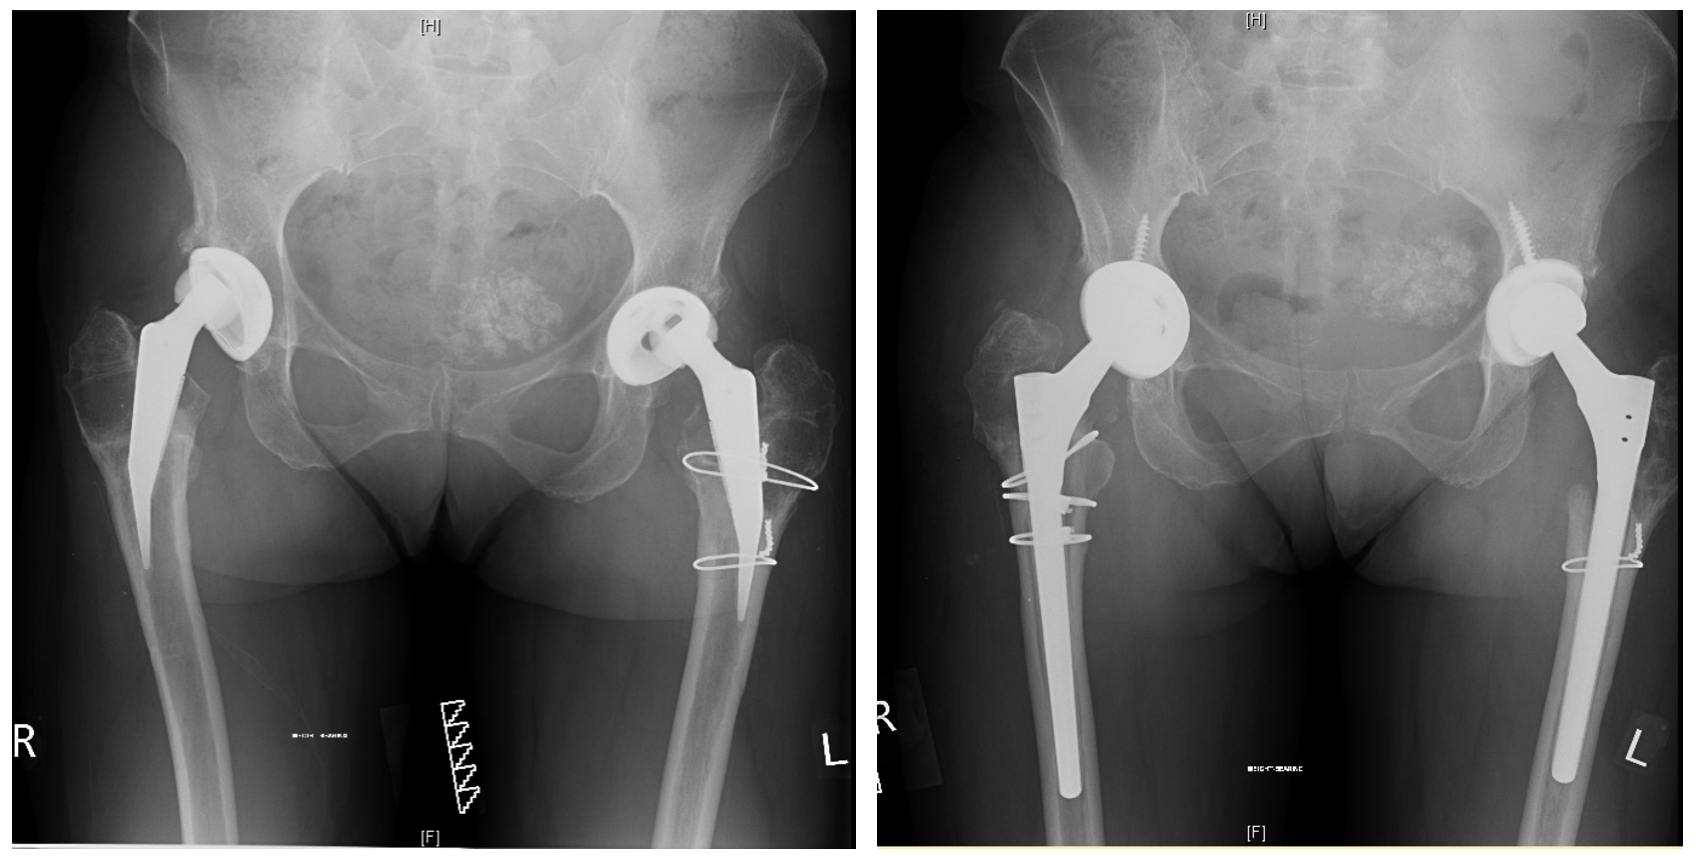

BILATERAL HIP REPLACEMENT

"Getting my life back"

I'm so trilled with my new hips I thought I'd email you to fill you in on what they are doing for me: Climbed a gate with ease about 2 weeks ago, something I haven't been able to do for a few years. Did a 16km canal walk last week with ease and even better no grumbling legs/joints afterwards

Bilateral Revision Hip Replacement

" I can't express this clearly enough: you've come to the right surgeon! "

In my many decades' experience with hip operations Mihai Vioreanu has stood out for two reasons: the exceptional skill he brings to his surgeries, and the depth of empathy, humanity and kindness he shows to his patients.